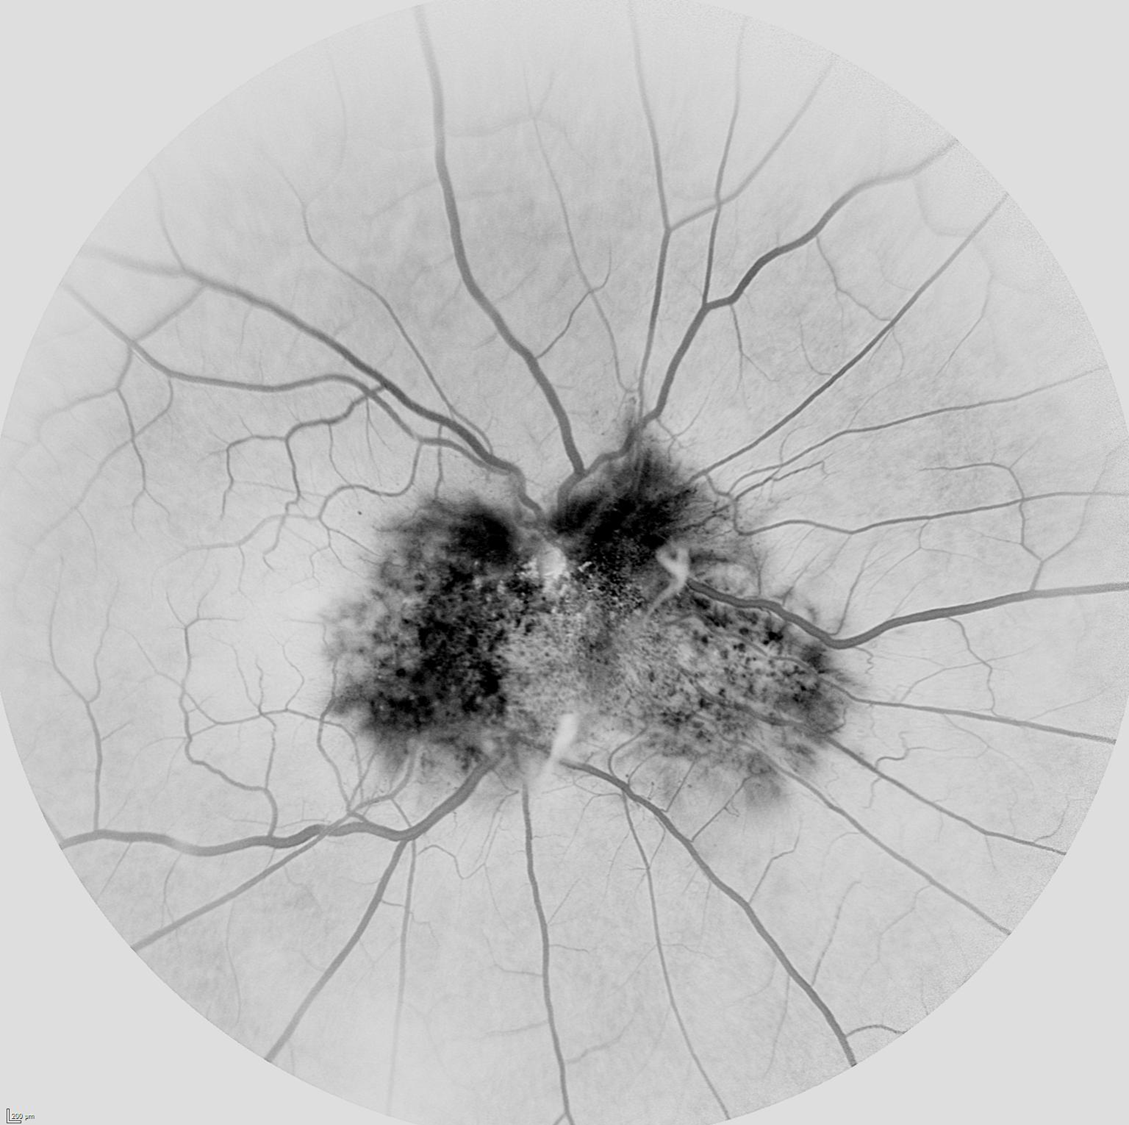

Angiografía fluoresceínica en hamartoma combinado de retina y epitelio pigmentario modo negro sobre blanco

Los hamartomas combinados de retina y epitelio pigmentario retiniano (CHRRPE) son raros tumores benignos, caracterizados por la proliferación del epitelio pigmentario retiniano (EPR) y tejido glial, generando gran distorsión papilar y retiniana. Se aprecia una lesión solitaria unilateral sobrelevada, hiperpigmentada, acompañada de tortuosidad vascular y membrana epirretiniana (MER).

La angiografía puede ayudar bastante en el diagnóstico observándose en las fases precoces hipofluorescencia en relación al grado de hiperpigmentación del tumor, tortuosidad vascular y telangiectasias. En la fase media se observan mejor las anomalías vasculares y según avanzan los tiempos los vasos suelen fugar dando lugar a una hiperfluorescencia tardía.